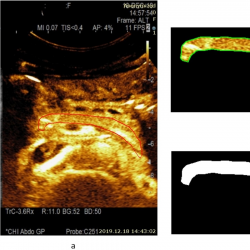

infor453_g003.jpg

Fig. 3

Example of a CEUS image (15 s after injection of contrast agent) of a healthy pancreas (healthy volunteer – female) and estimated area of a healthy parenchyma (according to the presence of perfusion): a – contrast harmonic image of the pancreas region and manually selected ROI according to the solid red line, b – extracted informative ROI for further automatic detection of healthy parenchyma areas being marked with a solid green line, c – automatically detected area of a healthy parenchyma is binary marked (white) and covers 100.0% of the overall pancreas ROI.

An example of a CEUS image of a healthy pancreas (healthy female volunteer) acquired at 15 s after injection of contrast agent and an estimated area of healthy parenchyma (according to the presence of perfusion) is presented in Fig. 3. The automatically detected area of healthy parenchyma is marked in white, with the area covering 100.0% of the overall pancreas ROI. The CEUS B-mode image of pancreas affected by acute pancreatitis (male patient) acquired 22 s after injection of contrast agent, and an estimated area of healthy parenchyma (according to the presence of perfusion) is presented in Fig. 4. Here, the automatically detected area of healthy parenchyma (white) covers 55.6% of the overall ROI. The remaining part of the tissue is affected by necrosis and covers 44.4% of the overall ROI.